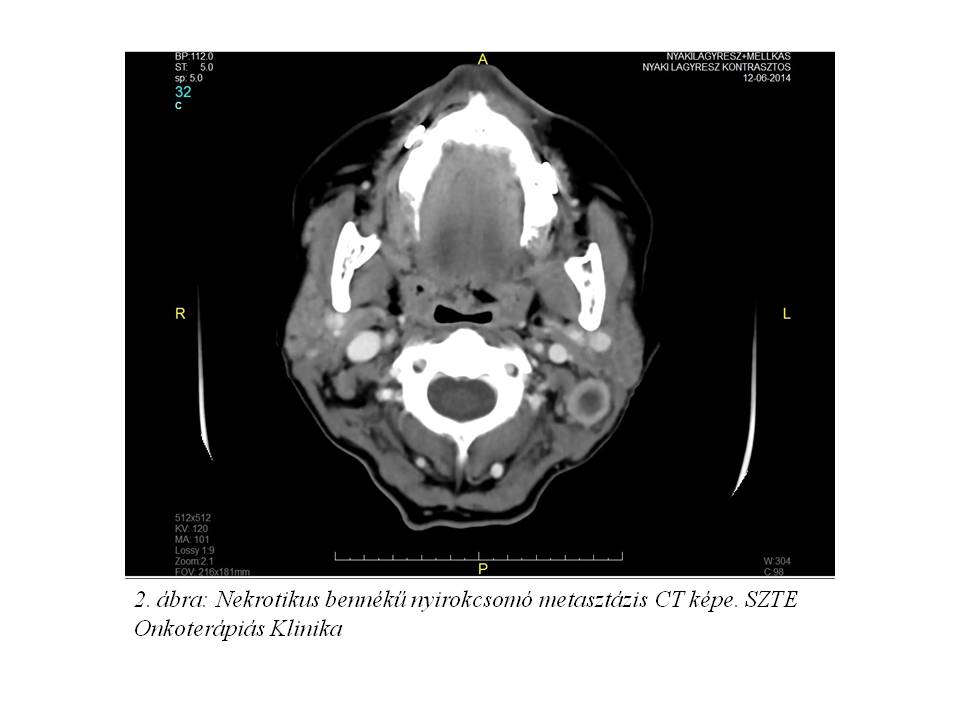

Esetismertetés: Jelenleg 52 éves, 30 éve dohányzó (napi 10 szál cigaretta), alkoholt nem fogyasztó, 20 évvel ezelőtt gyomorfekély miatt műtéten átesett, jelenleg hypothyreosissal kezelt nőbeteg esetét ismertetjük. A beteg 2014 júniusában jelentkezett fül-orr-gégészeten két éve tartó gombócérzés, időnként tapasztalt nyelési nehezítettség és fájdalom, a nyak bal oldalán 1 éve észlelt fájdalmatlan, kemény csomó, 2 hónap alatti 10 kg testsúlyvesztés, és 1 hónapja tartó, antibiotikus kezelésre nem szűnő, a bal fül felé sugárzó torokfájdalom miatt. Fizikális vizsgálat során a fejbiccentő izom elülső széle mentén a parajugularis régióban 2,5 cm átmérőjű, mobilis, ép bőrrel fedett nyirokcsomót észleltek. Rhino-pharyngo-laryngo-fiberoscopia során a bal oldali sinus piriformisban U-alakú, egyenetlen szövetszaporulat és nyálpangás igazolódott. Nyaki és mellkasi CT vizsgálat a hypopharynx régióban, a baloldali sinus piriformist kitöltő, a kontrasztanyagot homogénen és intenzíven halmozó, 20 x 14 x 20 mm nagyságú, a középvonalat meg nem haladó térszűkítő elváltozást, ebben a magasságban baloldalon a vena jugularis internát komprimáló, 20 mm átmérőjű, nekrotikus bennékű metasztázist, valamint a C.II csigolya szintjében dorsalisan egy 2 cm-es, patológiás szerkezetű nyirokcsomót írt le (1. ábra, 2. ábra). A tüdőkben metasztázisra utaló eltérés nem volt (T3 N2 cM0 stádium). Laryngomicroscopia során a bal oldali pharyngo-és aryepiglotticus redőn, illetve a sinus piriformis medialis falán elhelyezkedő teriméből szövettani mintavétel történt, mely közepesen differenciált laphámcarcinomát igazolt. Indukciós TPF kemoterápiát (docetaxel-cisplatin-5-fluorouracil) indítottunk, melynek 1. ciklusát követően a tapintható nyirokcsomó metasztázis eltűnt, a beteg nyelési fájdalmai megszűntek. A kemoterápia harmadik ciklusát követően fül-orr-gégészeti vizsgálat során makroszkópos tumor nem volt látható, az elvégzett PET/CT vizsgálat során FDG-avid malignitás nem igazolódott (3. ábra, 4. ábra). Jelenleg a beteg definitív sugárkezelését végezzük.